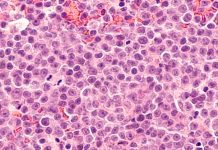

Cellular discovery in lymphomas could improve blood cancer treatment

New insights on the workings of aggressive lymphomas could lead to earlier cancer detection and improvements in treatment, researchers say.

In a study led by...